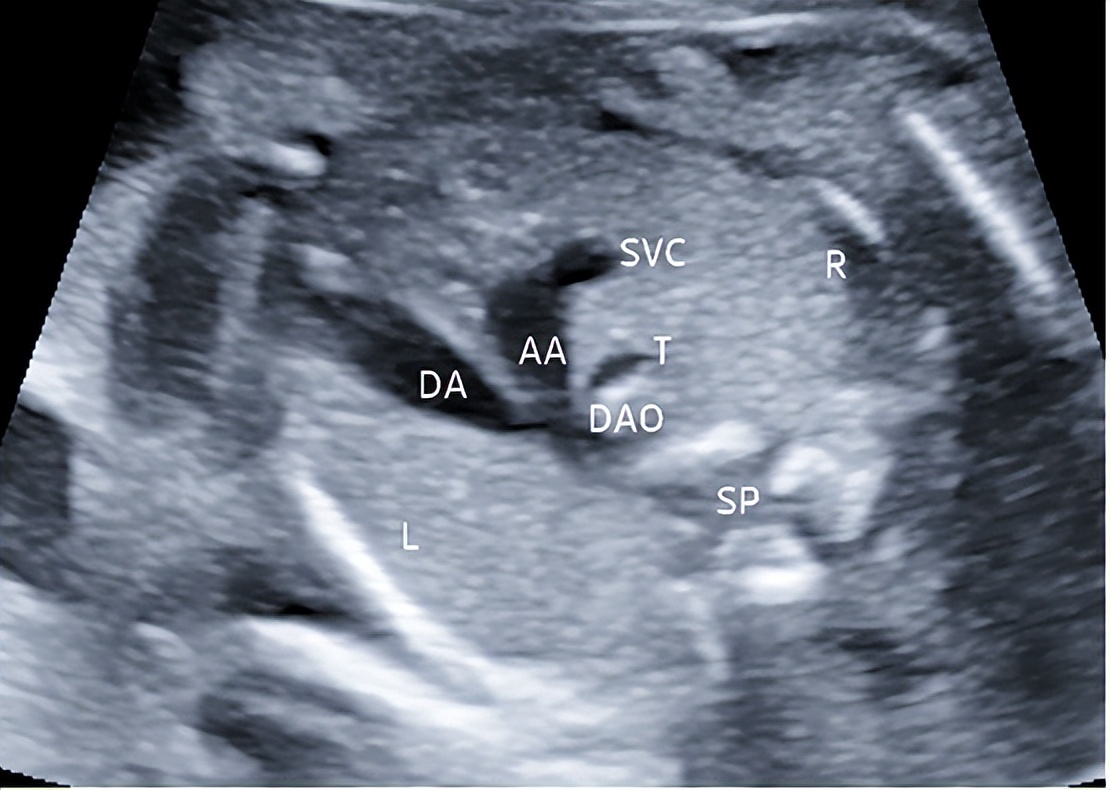

4.三血管气管切面

切面要求:显示主动脉弓和动脉导管弓的横弓及上腔静脉和气管横切面(图4)。

观察内容:主动脉弓和动脉导管弓共同汇入降主动脉,呈“V”形;从左向右血管的排列为:动脉导管弓、主动脉弓、上腔静脉;气管位于“V”形右侧、上腔静脉后方。

图4 孕23周三血管气管切面 显示主动脉弓和动脉导管弓的横弓及上腔静脉和气管横切面(DA:动脉导管;AA:主动脉弓;SVC:上腔静脉;DAO: 降主动脉;T: 气管;SP: 脊柱;L:左侧;R:右侧)